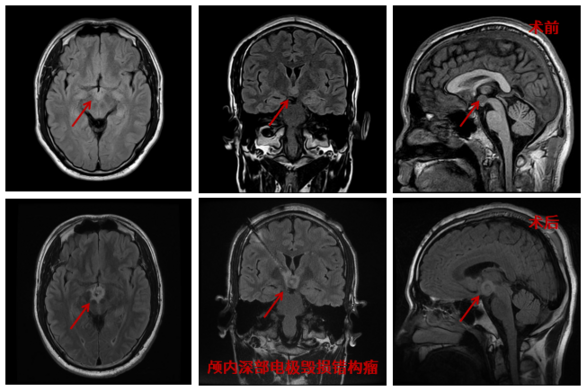

经过充足的术前准备后,三博癫痫中心团队运用此项技术,在机器人的“帮助”下,成功“消灭”了患者颅内的错构瘤,并满意解决了患者多年癫痫发作的问题。“相比于传统的开颅手术,新技术最大的特点就是精准、微创及安全。”关宇光主任介绍说,这是一种全新的肿瘤‘切除’方式,热凝毁损肿瘤的过程中患者甚至是清醒的,我们可以在术中检测他的语言、视力和运动功能有没有受到影响。这项手术能给患者带来更小的损伤、更好的预后。”